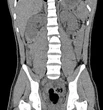

Bị bạn bè trêu chọc vì thân hình “không cân đối”, thiếu nữ 17 tuổi bắt đầu mặc cảm với cơ thể, giảm cân cực đoan rồi phải nhập viện với chẩn đoán chán ăn tâm thần.

Ám ảnh về ngoại hình, cân nặng quá mức có thể là biểu hiện của rối loạn hành vi ăn uống - Ảng: AFP